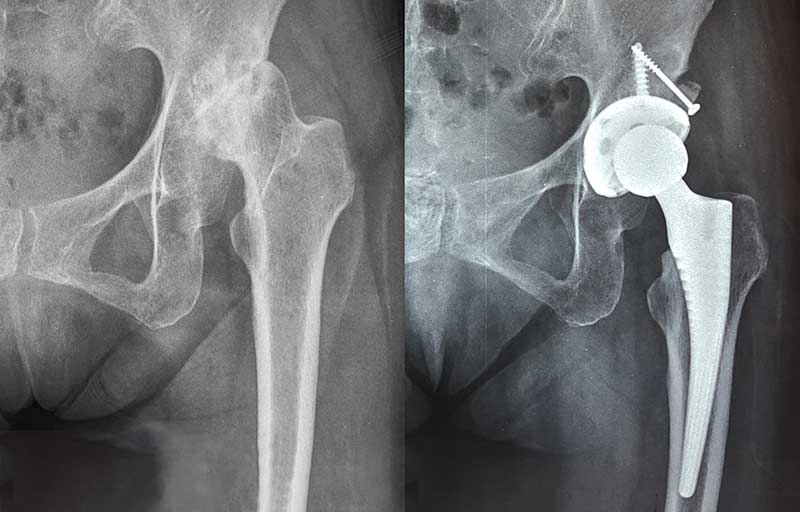

• Operasi penggantian sendi panggul adalah operasi yang dilakukan untuk mengganti sendi panggul yang telah mengalami kerusakan akibat pengapuran dengan sendi panggul buatan. Panggul merupakan sendi kedua tersering setelah lutut yang paling sering terserang pengapuran sehingga operasi penggantian sendi penggul merupakan operasi penggantian sendi yang paling banyak dilakukan setelah penggantian sendi lutut.

Operasi penggantian sendi panggul bermanfaat menghilangkan nyeri sendi akibat pengapuran sendi dan memperbaiki gaya jalan pincang akibat nyeri panggul tersebut.